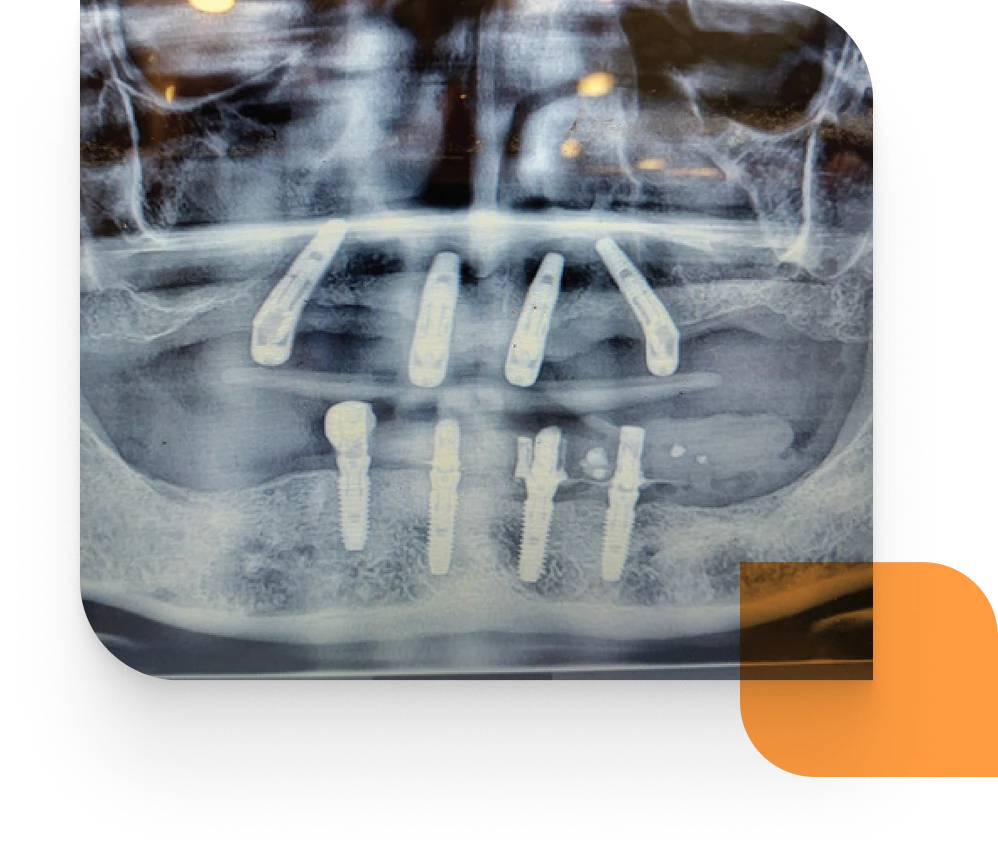

- Diagnose, treatment plan with CBCT scans and study models.

- Pretreatment and post treatment xrays.

The All‑on‑X Course is a week‑long live patient programme held at the University of Chennai, India. Participants typically place 12 implants and restore up to three full arches with immediate fixed provisional bridges. The learning includes CBCT‑based diagnosis and planning plus fully or partially guided implant placement, surgical suturing, prosthetic workflows and treatment from start to finish with specialist mentor support.